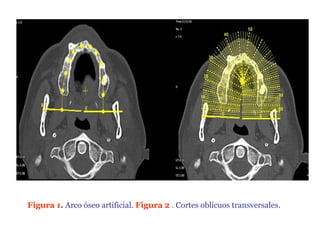

Figura 1. Arco óseo artificial. Figura 2 . Cortes oblicuos transversales.

TOMOGRAFIA Em 1987, atomografía é usada em Odontologia por Schartz, Rotman, Chafetz e Rodes